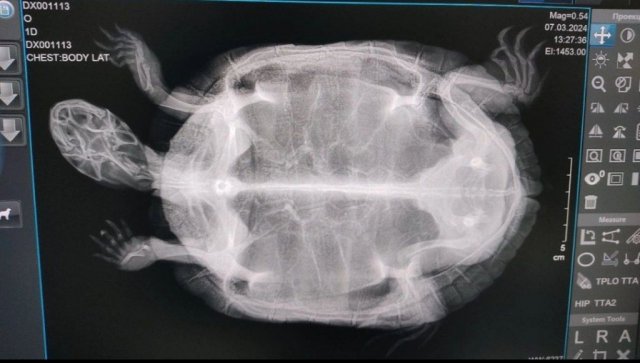

9. Обращались в ветеринарку, помочь не смогли. Проводили долго осмотр. Не смогли определить мальчик это или девочка. Сделали снимки, прикреплю фото. Сказали,что истощён, но это и нам понятно. Сделали клизму, зачем то засунули палец в попу. На этом все. Никаких лекарств не назначили. Сказали, что воспаления нет.

С такими симптомами чаще всего да, проблемы с жкт - непроходимость или атония или пережимается фолликулами, если есть ещё и проблемы с репродуктивной системой. Жалко они Вам не сделали в другой проекции ещё снимок. На этом не видно лёгких.